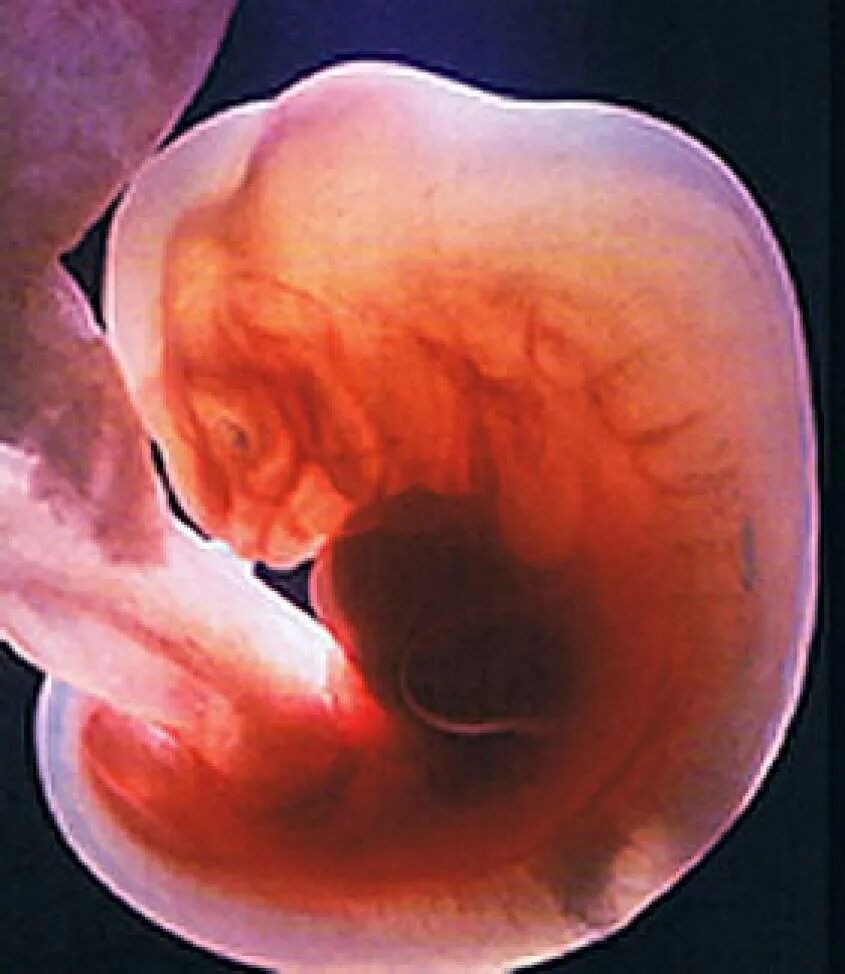

Беременность 4 недели что происходит с плодом